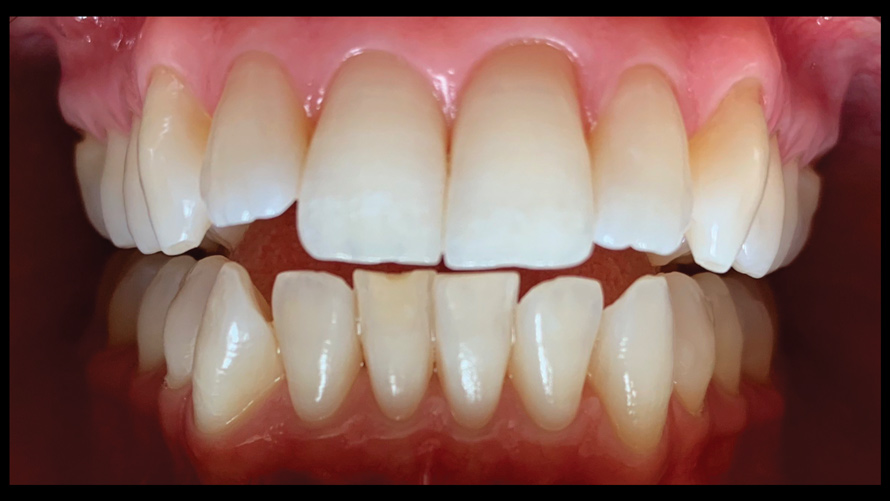

Shade Selection and Laboratory Communication

The most utilized intraoral photographs in the field of dentistry are perhaps those that capture shade information (Figure 18 and Figure 19). The analysis of color (ie, value, chroma, hue) in dentistry is a critical step in the fabrication of esthetic indirect restorations, such as all-ceramic crowns and porcelain laminate veneers. The ability to properly communicate this information with the dental laboratory is essential to ensure an appropriate shade match, a reduction in chairtime and overhead, and most importantly, a satisfactory patient experience and treatment outcome. In recent years, the use of polarized light photography as an aid in the shade selection process has become extremely popular. For some EALS devices, special polarizing filters have been specifically designed to fit over the light-emitting portion of the device (Figure 20 and Figure 21). The images produced using polarized light photography demonstrate an elimination or reduction in the specular reflection of hard and soft tissue, resulting in a matte-finish appearance of the dentition and gingiva. These types of photographs aid the ceramist in identifying areas of opacity and translucency, crack lines, hypo- or hypercalcification, and other internal features of the dentition that may not be readily visible without such a filter (Figure 22).

(18.) Tooth shade analysis of value, chroma, and hue taken with a smartphone and an EALS device.

Figure 18

(19.) Tooth shade analysis of value, chroma, and hue taken with a smartphone and an EALS device.

Figure 19